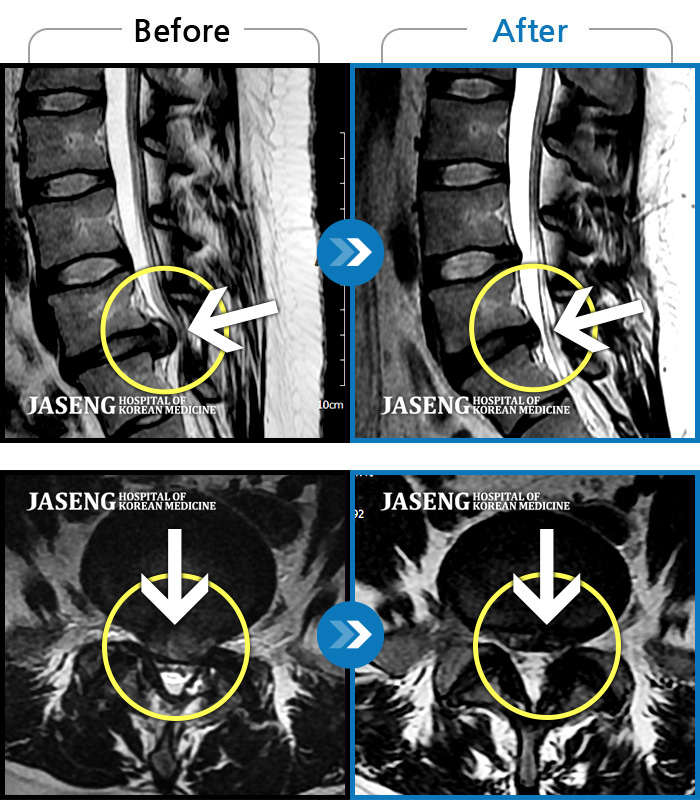

허리디스크

도움받은 사례

목동 · 고웅 원장

심한 허리 통증

촬영시기

2022.12.23 ~ 2024.12.04

2024.12.24